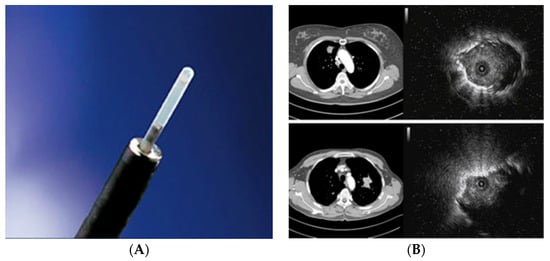

2.2. Radial Probe—Endobronchial Ultrasound with a Guide Sheath in the Diagnosis of Peripheral Lung Lesions

RP-EBUS-GS—Guided Endobronchial Ultrasound in the Era of Molecular Testing of Tumor Tissue

- Kurimoto, N.; Murayama, M.; Yoshioka, S.; Nishisaka, T. Analysis of the internal structure of peripheral pulmonary lesions using endobronchial ultrasonography. Chest 2002, 122, 1887–1894. [Google Scholar] [CrossRef]

- Kikuchi, E.; Yamazaki, K.; Sukoh, N.; Kikuchi, J.; Asahina, H.; Imura, M.; Onodera, Y.; Kurimoto, N.; Kinoshita, I.; Nishimura, M. Endobronchial ultrasonography with guide-sheath for peripheral pulmonary lesions. Eur. Respir. J. 2004, 24, 533–537. [Google Scholar] [CrossRef]